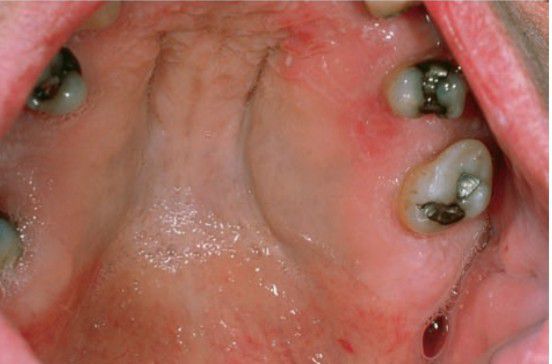

Neurofibroma of palate

Oral lesions are typically associated with neurofibromatosis type 1 (NF-1). This condition includes multiple neurofibromas, cutaneous café-au-lait macules, bone abnormalities, central nervous system changes.